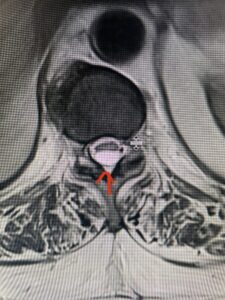

Fig 4. Axial T2-weighted MRIs demonstrating large C5-6 herniated disc with spinal cord compression (red arrow)

This 36-year-old female who had a long history of neck pain had a history on MRI of a C5-6 bulge. She recently after diving into a pool (not hitting her head on bottom) developed progressive problems with her arms. She had developed spontaneous shocks going down her arms and in the back of her neck. Spontaneous shocks going down the neck and spine is called a Lhermitte’s phenomenon and can occur with spinal cord compression and also with multiple sclerosis. On examination, the patient had long tract weakness of her arms, right greater than left. Her finger extensor weakness was profound on the right. MRI (Fig. 4) of the cervical spine revealed a massive C5-6-disc herniation causing significant cord compression right greater than left with subtle cord signal change. Because of the severe myelopathy, the patient was indicated for surgery. A C5-6 anterior cervical discectomy and fusion was performed (Fig. 5). The patient had a dramatic improvement of her strength in the recovery room.